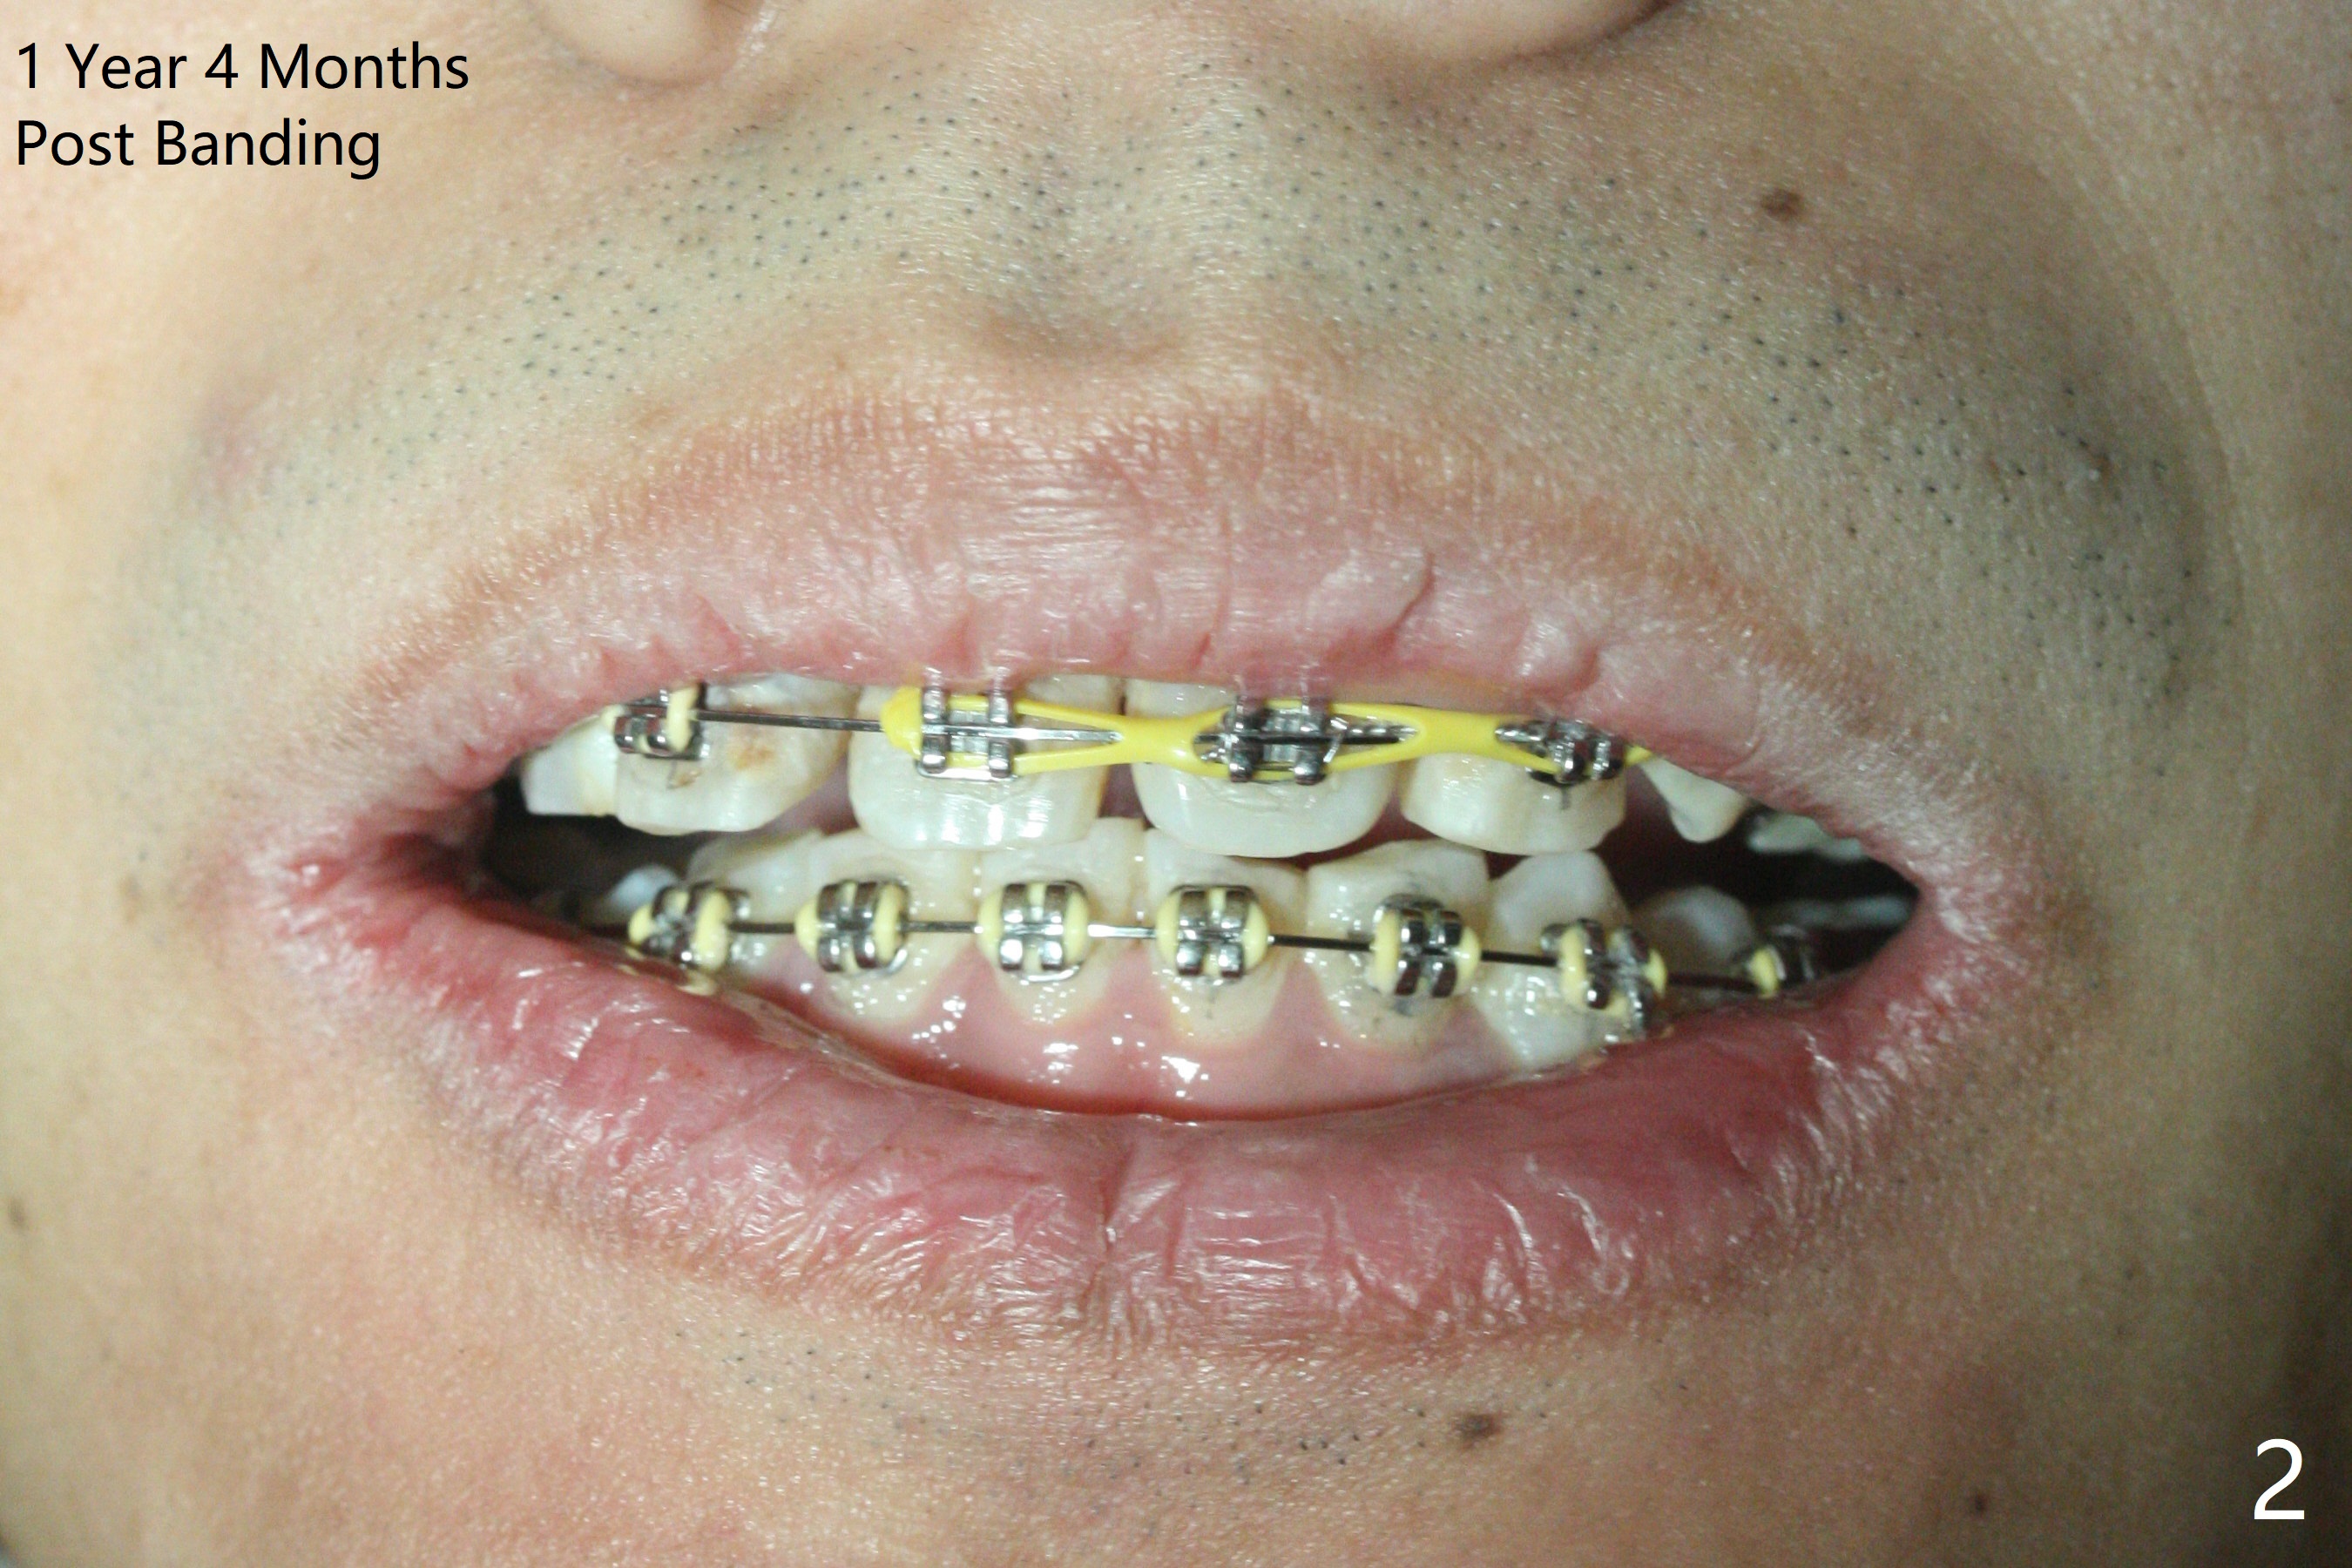

One year 4 months post banding (M) with 16x16 wires, UR3 is being distalized using UR7 as anchor (Fig.1), while the upper dental midline matches the facial one (Fig.2). The anterior overjet remains large (Fig.3). When UR3 is fully distalized, place posted wire to distalize U2-2 together. U2-2 distalization seems to be slow with one 16 mm closed coil spring each side (between 7 and post) 1 year 10 months post banding. Since the upper anterior PA shows mild root resorption at UR2 (Fig.4), a 14 mm closed coil spring is added each side (between 6 and post, Fig.5,6). LR6 has pain 2 years 2 months post banding (Fig.7). Debridement confirms non-salvageability; a 5x11.5 mm implant will be near the mesial root (Fig.8). Power chains for a month leads to closure of the gap between 3 and 4 (Fig.8-11). The space between 4 and 7 is 15 mm. A 12 mm 1st molar crown will be made, while the remaining 3 mm space will be closed by mesialization of 7 using 2 power posts mesial and distal to 6 and 7. Draw 2 tubes of blood. Make an incision to expose the mesial crest of 6.